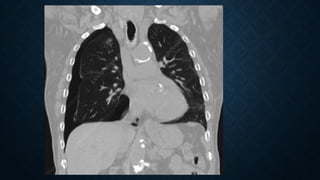

POSITION OF NG TUBE